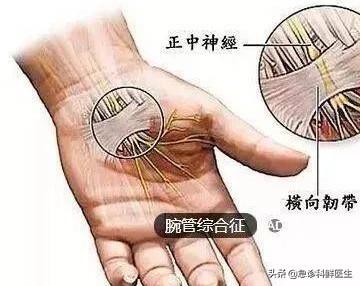

正中神経損傷: 前腕と上腕の正中神経は、外傷、腫瘍、圧迫などにより、手掌面、親指、人差し指、中指にしびれや痛みを生じる。手首は、手根管症候群と呼ばれる損傷や圧迫に対して最も脆弱であり、治療原則は以前と同じです。

手根管の正中神経が圧迫されることによって、人差し指と中指の痛みやしびれ、親指の筋力低下が起こる症状である。

手のしびれは、手首付近の前腕から手のひらにかけて走る神経が圧迫されることによって誘発され、痛み、灼熱感、ピリピリ感などの不快感を伴い、時には手の脱力を伴うこともある。

神経損傷というと、外傷、腫瘍、手根管症候群などが神経損傷につながる可能性があり、特に正中神経、尺骨神経、橈骨神経が損傷され、指がしびれたり、痛んだりすることがあります。手根管症候群は、例えば、その形成の主な理由は、患者の手首の正中神経が圧迫されるにつながる長い時間の手首の不適切な使用であり、この種の患者は、しびれ、あるいは痛みの3本の指の親指側に表示されます。

3つ目は手根管症候群で、手根管が圧迫され、手根管を通る神経が損傷し、指のしびれや痛みが生じる。

親指、人差し指、中指の半分は正中神経に支配されている。

最も多いのは手首の神経巻き込みで、手首にはブレスレットのような靭帯があり、手首の神経や血管を縛っている。 この縛りがきつすぎると巻き込みが起こり、通常、神経、靭帯、腱が長時間摩擦されることで炎症や水腫が起こり、その結果、押し出されて神経が巻き込まれる。

手根管症候群と呼ばれる正中神経の圧迫の場合、親指側の3本の指のしびれや、親指側の手掌面の筋萎縮が起こることもある。

手根管症候群のテスト。手首を曲げて手の甲をぎゅっと手の甲に当ててみて、しびれの方が強ければ、基本的に手首が詰まっています。

3.手根管症候群

手根管症候群は、人口のいくつかの長期的な両手操作で一般的であり、手根管の炎症につながる活動の姿勢を維持するために、長期的な手首に起因するか、または汚れと神経の圧迫現象は、手根管症候群の患者は、初期の手首の感覚の柔軟性の欠如、および皮膚の感覚異常で表示され、夜間にはピンピックの痛みの症状があり、病気の悪化に伴い、親指、人差し指、中指の徐々にしびれがあるだろうし、腕の痛みや不快感に関与している。腕の痛みや不快感も関与してきます。